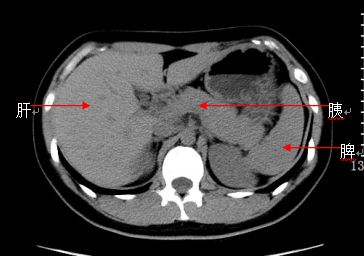

5)胰腺炎:急性胰腺炎主要由胆系疾病或饮酒引发,可分为水肿型胰腺炎和坏死型胰腺炎。

CT表现:水肿型胰腺炎少数轻型患者CT可为阴性,多数病例有不同程度的胰腺体积增大,密度正常或轻度减低,可伴有胰腺轮廓模糊,周围渗出积液,增强后胰腺实质强化均匀;坏死型胰腺炎胰腺体积常明显增大,密度不均匀,可见低密度坏死区,胰腺周围较多渗出积液,胰腺边界模糊,增强后坏死区无强化。

急性水肿型胰腺炎:CT平扫,胰腺明显肿胀,密度尚均匀,周围见条片渗出。

急性坏死型胰腺炎:CT平扫,胰腺密度不均匀减低,胰腺边界模糊,胰腺周围较多渗出积液,肝周可见积液。